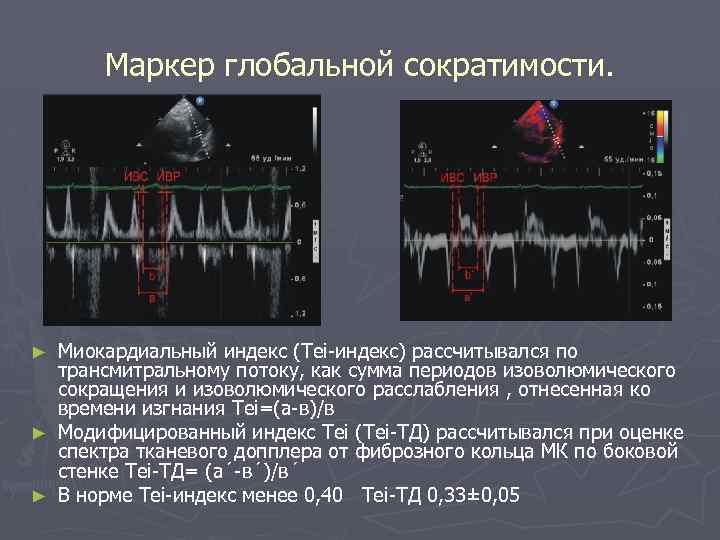

Маркер глобальной сократимости. Миокардиальный индекс (Tei-индекс) рассчитывался по трансмитральному потоку, как сумма периодов изоволюмического сокращения и изоволюмического расслабления , отнесенная ко времени изгнания Тei=(а-в)/в ► Модифицированный индекс Тei (Tei-ТД) рассчитывался при оценке спектра тканевого допплера от фиброзного кольца МК по боковой стенке Tei-ТД= (а´-в´)/в´ ► В норме Тei-индекс менее 0, 40 Tei-ТД 0, 33± 0, 05 ►